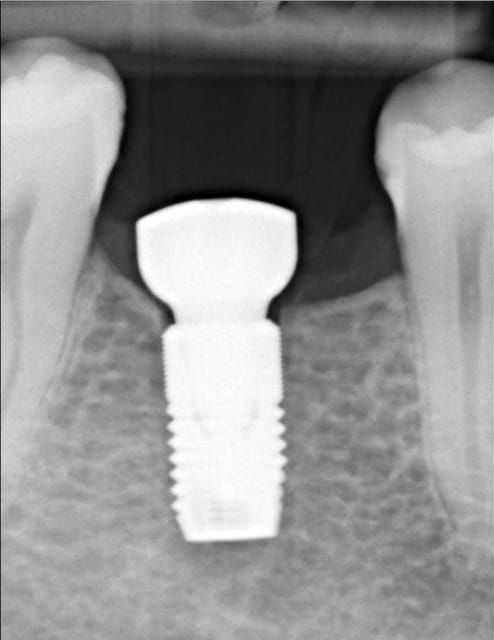

Bon je m'y colle, c'est pas le même niveau qu'olivier, mais ce sujet étant censé être pour les débutants je poste.

Patient 26 ans, à qui il manque 46, 25 et 26.

Pour l'instant je vous propose la partie préparation et mise en place de l'implant en 46, la suite peut être bientôt.

Dans l'ordre si le site veut bien, wax-up ( cirage pour céramik ;) ) , guide radio, et scan.

Photos pré-op, indicateur de direction en place et post-op.

Il s'agit d'un implant astra osseospeed de 5 mm de diamètre et 9 de long.

Prothèse prévue à 6 semaines.

puisque tu veux de la critique, impec (juste que je l'aurais mis à peine, mais vraiment à peine moins infra-osseux)

c'est à cause du profil de la crête, en fait l'implant est juxta-osseux en vestibulaire, par contre moi je le trouve ( légèrement ) trop distal.

bonne iconographie et bon travail, même si légèrement distal.

j'aurais mis un peu plus long (12?)